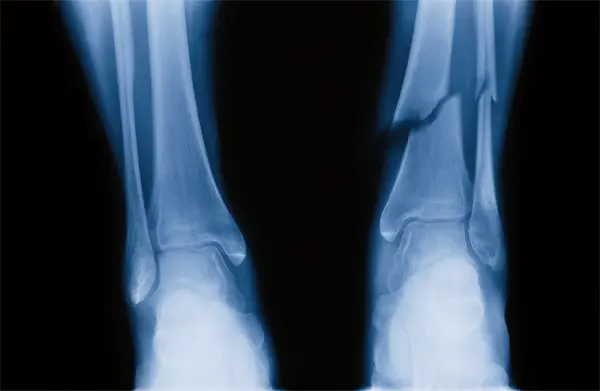

The most common method for height increase is leg-lengthening surgery. This procedure typically involves the following stages:

- Osteotomy: The surgeon makes a precise cut in the bones of the legs.

- Latency Period: After surgery, there is a resting phase for recovery.

- Distraction: A device is attached to the bone to gradually pull it apart over time.

- Consolidation: The new bone grows and hardens in the gap created.

Patients can achieve a height increase of up to five inches (13 cm) through this surgical process. The overall time for recovery and adjustments can vary, often lasting months, depending on individual circumstances. Costs for this type of surgery can range from $50,000 to $100,000, depending on the location and necessary treatments.

The surgical process typically involves limb shortening techniques. Surgeons may remove a section of bone from the legs to achieve the desired height reduction.

- Anesthesia: The patient is given anesthesia to ensure comfort during the operation.

- Incision: A small incision is made in the skin over the bone to shorten.

- Bone Removal: A precise section of bone is carefully removed.

- Stabilization: The remaining bone segments are realigned and stabilized with plates or screws.